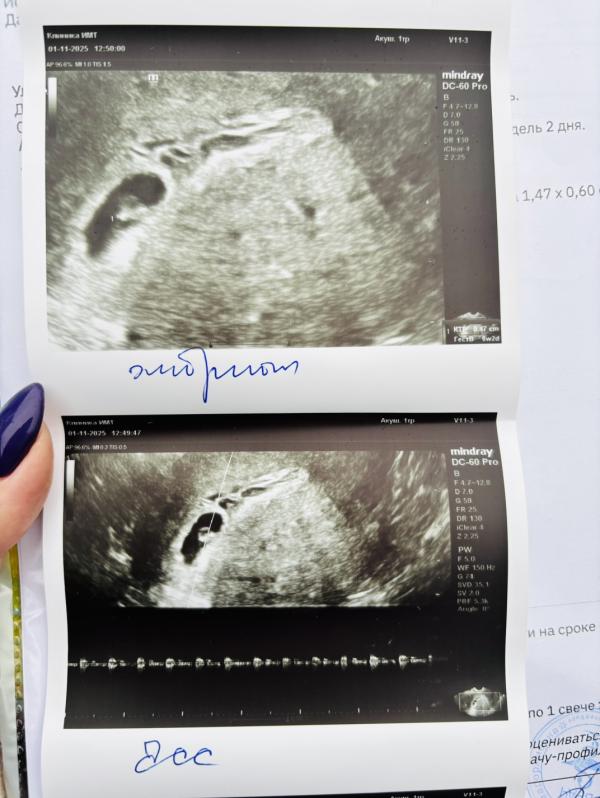

Моя пуговка 💜

Малышик 🥹 а внизу написано Чсс?

01.11.2025 Нравится Ответить

Да

Врач подписала фото для гинеколога

@viktoria_klockova, супер 🥰 то есть в 6 недель уже по идее можно СБ увидеть ?

@le0doma, да можно

Я сама в шоке была , что его видно и слышно 🥹🥹🥹